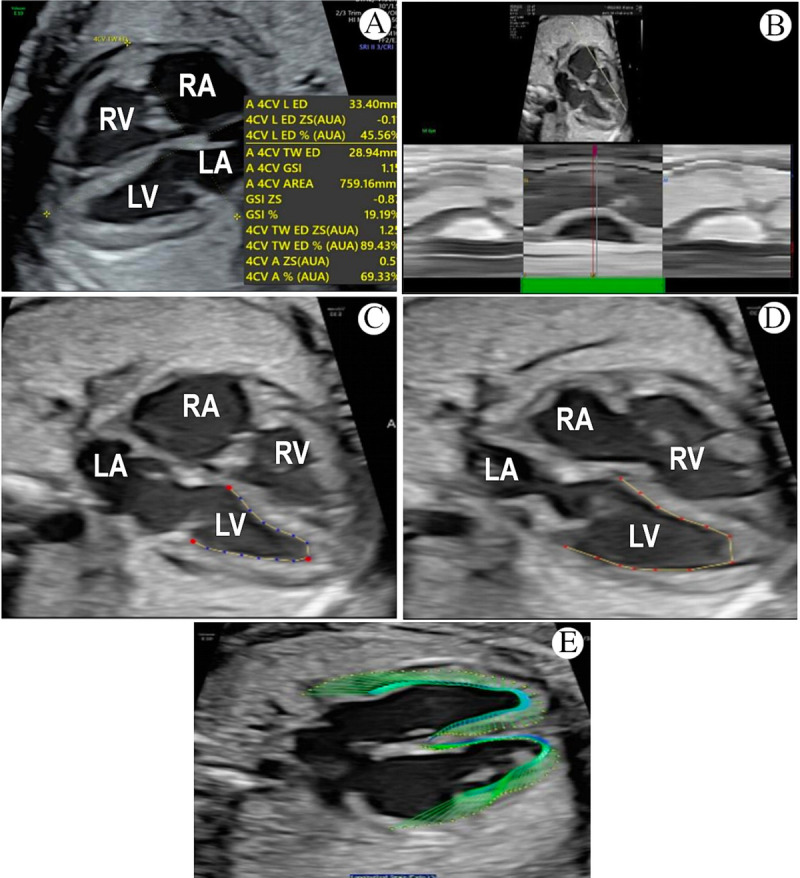

Objective: To use fetal heart quantification (fetal HQ) technology to compare the coarctation of the aorta (CoA) and normal fetal heart structure and systolic function and to assess whether there are abnormalities in the fetal heart structure and systolic function associated with CoA.

Methods: This prospective cohort study was conducted from May 2020 to December 2022 and involved 18-40-week-old singleton pregnancies and 30 fetuses diagnosed with CoA using fetal echocardiography at the General Hospital of Ningxia Medical University and Peking University First Hospital Ningxia Women's and Children's Hospital, China. The control group contained 60 normal fetuses. The following parameters were recorded and analyzed statistically: four-chamber view (4CV) end-diastolic long diameter, 4CV epicardial-contralateral epicardial transverse maximum diameter, 4CV global sphericity index (GSI), left ventricular (LV) and right ventricular (RV) 24-segment end-diastolic diameter (EDD), 24-segment sphericity index (SI), LV-fractional area change (LV-FAC), LV-longitudinal strain (LV-LS), RV-fractional area change (RV-FAC), RV-longitudinal strain (RV-LS), and LV and RV 24-segment transverse fractional shortening (FS). Measurement data were compared between the two groups using an independent sample t test, with P < 0.05 indicating statistically significant differences. Moreover, the correlation between gestational age and GSI, LV-FAC, LV-LS, RV-FAC, and RV-LS was assessed.

Results: Within and between observer comparisons of the parameters associated with major cardiac function revealed an intragroup correlation coefficient of >0.9, indicating high consistency, and a coefficient of variable of <1%, indicating low variability. Correlation analysis revealed no obvious correlation between gestational age and GSI, LV-FAC, LV-LS, RV-FAC, and RV-LS. A comparison of the four-chamber morphological structural parameters of the hearts in the two groups revealed that when compared with the control group, the 4CV end-diastolic long diameter was shortened in fetuses in the CoA group and the epicardial-contralateral epicardial transverse maximum diameter was wider, while the GSI was lower (P < 0.05). A comparison of the LV and RV morphological structure parameters between the two groups revealed that when compared with the control group, the LV's 24-segment EDD was smaller in the CoA group, the RV's 24-segment EDD was greater in the control group, the SI of the LV's segments 16-24 was greater than in the control group, and the SI of the RV's segments 7-24 was less than in the control group (all P < 0.05). When compared with fetuses in the control group, the LV's segments 16-24 were greater in the CoA group, whereas the RV's segment 6-24 was smaller (P < 0.05). When compared with the control group, LV-FAC, RV-FAC, and LS were lower in the CoA group (P < 0.05). The FS of the LV segments 1-24 and the FS of the RV segments 1-16 were smaller in the CoA group than in the normal group (P < 0.05).

Conclusion: Fetal HQ, a new simple technique that offers rapid analysis and high repeatability, can quantitatively evaluate structural and systolic function changes in fetuses with CoA.